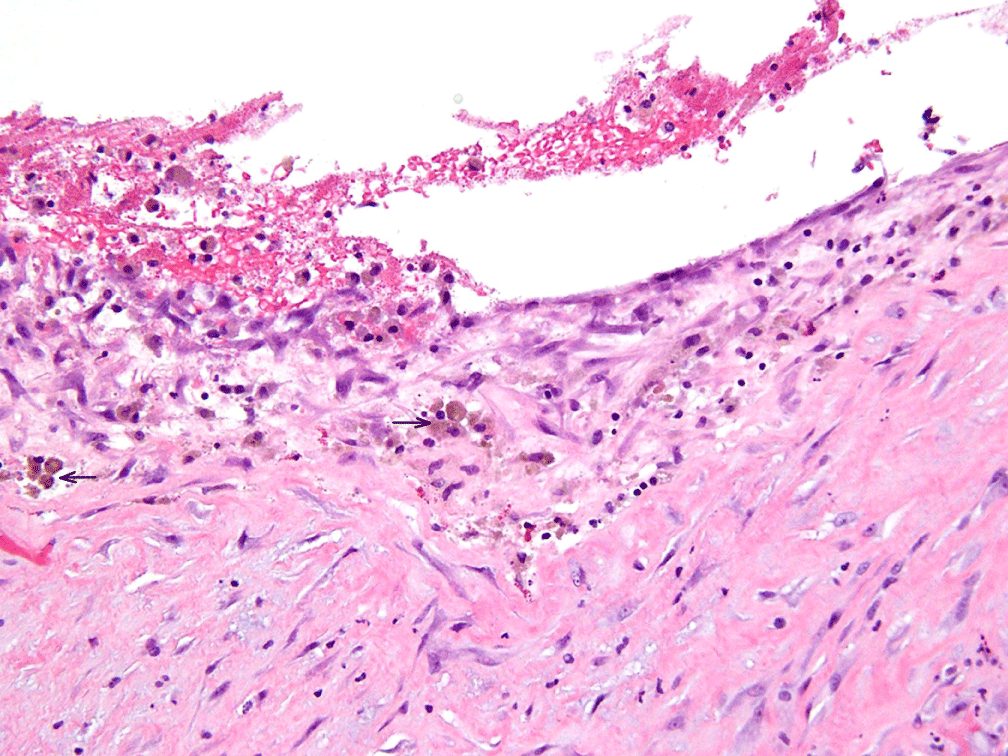

The patient underwent diagnostic laparoscopy with a preoperative differential diagnosis of atypical hemorrhagic cyst versus neoplasm. At surgery a 5 cm × 5 cm × 3 cm chocolate colored cyst was identified on the surface of the bladder serosa consistent in appearance with an endometrioma. The presumed endometrioma was also adherent to the left round ligament and the fundus of the uterus but was not in any way contiguous with the left ovary which was normal. The uterus, fallopian tubes, and right ovary were also normal in appearance, and there was no evidence of peritoneal or other intraabdominal endometriosis. There was no suggestion of a malignancy. During the process of resecting the mass, the cyst ruptured and dark-sanguinous fluid was visualized. The mass was removed, and fluid was evacuated. Pathological evaluation confirmed endometriotic cyst, with evidence of atrophic glands, hemosiderin laden macrophages (pigmented histiocytes) (Figure 3) and endometrial stroma with inflammatory response (Figure 4). The patient's postoperative course was uncomplicated and she was discharged home on the day of surgery on oral contraceptive pills. The patient recovered well and she was without pain on follow up exam.

Figure 3: 20X magnification image with evidence of blood, stroma, containing (arrow) hemosiderin laden macrophages (pigmented histiocytes). View Figure 3